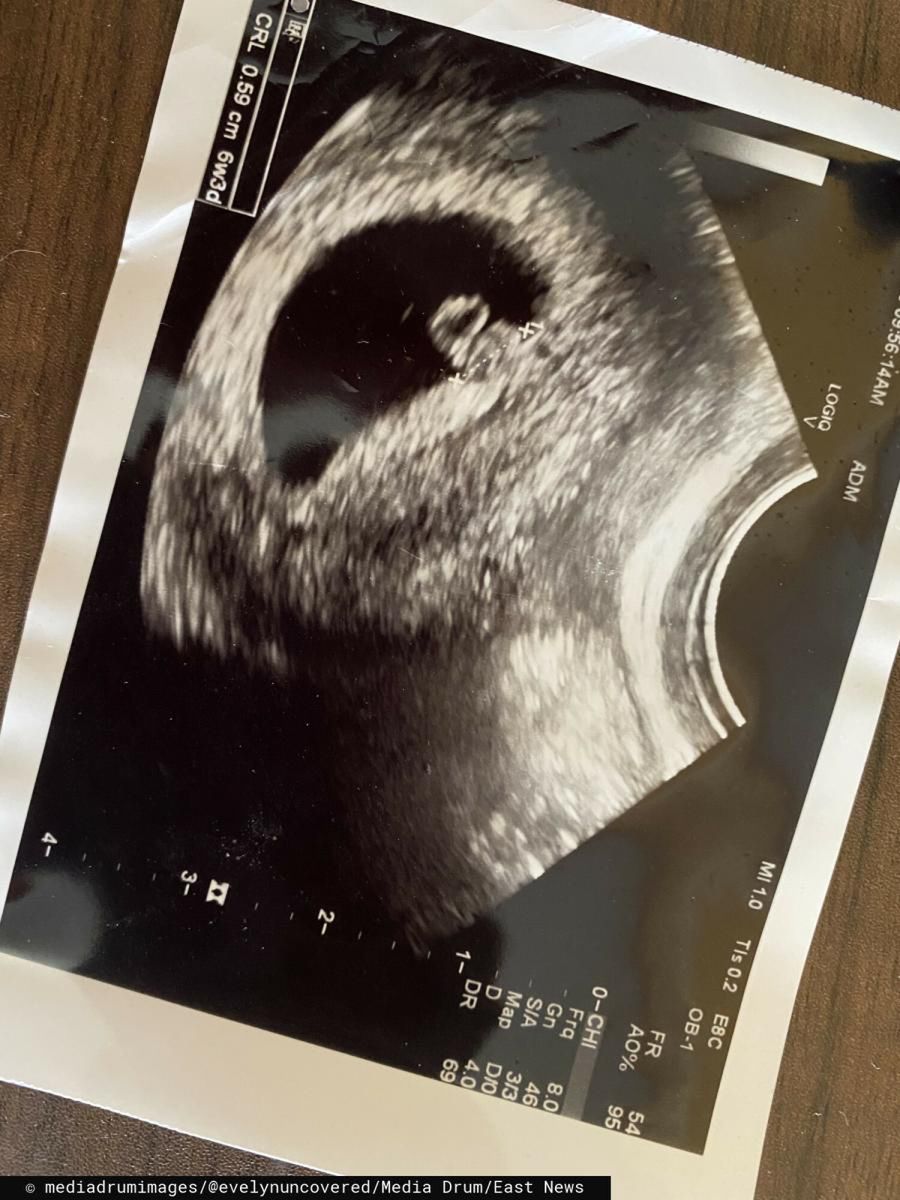

Obecnie Evelyn jest w ciąży i razem z partnerem czeka na narodziny dziecka.

Nie podejrzewała, że uda jej się zajść w ciążę © East News